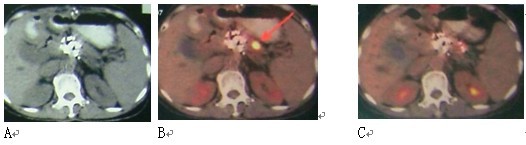

图3 女性,59岁。胰腺头部4X4 cm病变,活检显示未分化腺癌。A:治疗前;B:冷冻-碘粒子治疗后12个月复查PET-CT,原先病变无明显活性,但在胰腺体部出现新病变,给予冷冻治疗;C:3个月后复查PET-CT,病变活性抑制。患者生存28个月。